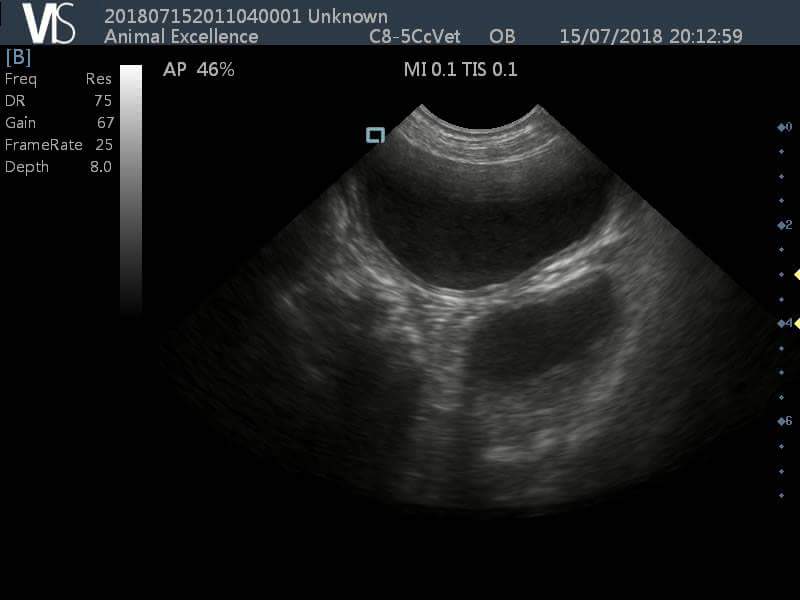

USG image of uterine stump pyometra in case no. 2 Download Scientific What Is A Stump Pyometra  The uterus is generally filled with pus.    — pyometra, characterized by the accumulation of purulent exudate in the uterus, is the most prevalent reproductive.  stump pyometra is suspected when a mass is seen on radiographs or ultrasound in the area of the uterine stump and there are. Treatment for a pyometra usually.  a true stump pyometra is. What Is A Stump Pyometra.

(PDF) Ultrasonographic evaluation of the uterine stump pyometra in What Is A Stump Pyometra   stump pyometra is suspected when a mass is seen on radiographs or ultrasound in the area of the uterine stump and there are. Treatment for a pyometra usually.    — in rare cases, a dog who has already been neutered may also develop a particular type of pyometra called a stump.  a pyometra (or “pyo”) is a womb. What Is A Stump Pyometra.